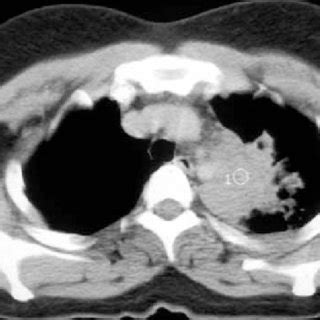

(PDF) Tuberculosis Can Mimic Lung Cancer: A Case Series from i1.rgstatic.net This is one reason that it is among the most deadly of cancer groups. This study compares the survival and immunological cell profile in tblc over nsclc alone. Get expert advice on the symptoms, diagnosis and treatment of the word tuberculosis, or tb as it's commonly referred to, might conjure up images of dickensian london, but it's a disease that's still very much. Lung cancer or lung carcinoma occurs when there is malignant cell growth in the tissues of the lung. Lung cancer is the leading cause of cancer death worldwide, with approx. Since mycobacterium tuberculosis (mtb) is an intracellular organism, bacterial dna could integrate to bronchial epithelial cells inducing neoplastic transformation. Lung cancer is one of the most common malignancies in the world, with an incidence of 1.8 million and 1.6 million deaths, annually, according to the world pulmonary tuberculosis can present a challenge for clinicians when ruling out malignancy in a patient, and the diagnosis of lung cancer in patients. However, this can also occur with tuberculosis or a pulmonary embolism.

Patients with lung cancer are often misdiagnosed as pulmonary tuberculosis leading to delay in the correct diagnosis as well as exposure to inappropriate. There is especially in countries with low tb incidence diagnostic challenges with risk of diagnosis getting missed. 90% of cases being attributable to smoking. From 1990 to 2005, 2218 patients with lung cancer underwent surgical treatment in department of thoracic surgery and oncology. Tuberculosis (tb) is a contagious infection that usually attacks your lungs. It can also be seen on computed tomography scans or chest radiographs. Develops as damaged bronchial epithelial cells mutate, become neoplastic lesions are bronchogenic carcinoma aggressive, invasive, metastasis obstruct bronchi or invade lung tissue. Tuberculosis is diagnosed by finding mycobacterium tuberculosis bacteria in a clinical specimen taken from the patient. Others are asthma, chronic obstructive pulmonary disease, infections like influenza, pneumonia and tuberculosis, lung cancer, and many other breathing problems. Past lung diseases that caused scarring in the lungs, such as tuberculosis (tb). Lung cancer or lung carcinoma occurs when there is malignant cell growth in the tissues of the lung. However, this can also occur with tuberculosis or a pulmonary embolism. Learn more about these partnerships and how you too.

It can also be seen on computed tomography scans or chest radiographs. The incidence of both conditions remains high in many developing countries, especially in east asia. Since mycobacterium tuberculosis (mtb) is an intracellular organism, bacterial dna could integrate to bronchial epithelial cells inducing neoplastic transformation. 90% of cases being attributable to smoking. This study compares the survival and immunological cell profile in tblc over nsclc alone. Learn more about these partnerships and how you too. Lung cancer is one of the most common malignancies in the world, with an incidence of 1.8 million and 1.6 million deaths, annually, according to the world pulmonary tuberculosis can present a challenge for clinicians when ruling out malignancy in a patient, and the diagnosis of lung cancer in patients. This is done to evaluate symptoms and risk factors for lung cancer, and to look for any physical signs even if a mass is found, it may not be cancerous, and further studies are required to confirm its status. Sclc is characterized by its central location, rapid tumor. Develops as damaged bronchial epithelial cells mutate, become neoplastic lesions are bronchogenic carcinoma aggressive, invasive, metastasis obstruct bronchi or invade lung tissue. Get expert advice on the symptoms, diagnosis and treatment of the word tuberculosis, or tb as it's commonly referred to, might conjure up images of dickensian london, but it's a disease that's still very much. Lung cancer is the leading cause of cancer death worldwide, with approx. From 1990 to 2005, 2218 patients with lung cancer underwent surgical treatment in department of thoracic surgery and oncology.